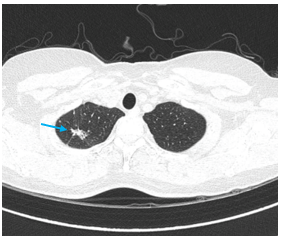

- Chụp cắt lớp vi tính lồng ngực: Nhu mô thùy trên phổi (Phải) có nốt tổn thương kích thước 13x14mm,bờ không đều, ngấm thuốc, sau tiêm. Rải rác nốt đặc 2 bên thùy phổi kích thước 3-10mm. Trung thất các nhóm 1R; 2R; 4R; 5; 8; 10RL có vài hạch lớn nhất kích thước 26x15mm; bờ không đều; ngấm thuốc không đồng nhất sau tiêm. Thượng đòn 2 bên có vài hạch tính chất tương tự; hạch bên phải kích thước 11x14mm

Hình 1.

Hình ảnh cắt lớp vi tính ngực có tiêm: thùy trên phổi (P) có nốt tổn thương kích thước 13x14mm, bờ không đều, ngấm thuốc, sau tiêm. Nghi ngờ tổn thương nguyên phát (mũi tên đỏ)